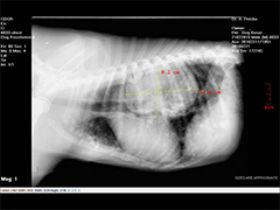

גידול בבית חזה אצל כלב עקב נגיעות כרונית בתולעת הפארק- ספירוסרקה